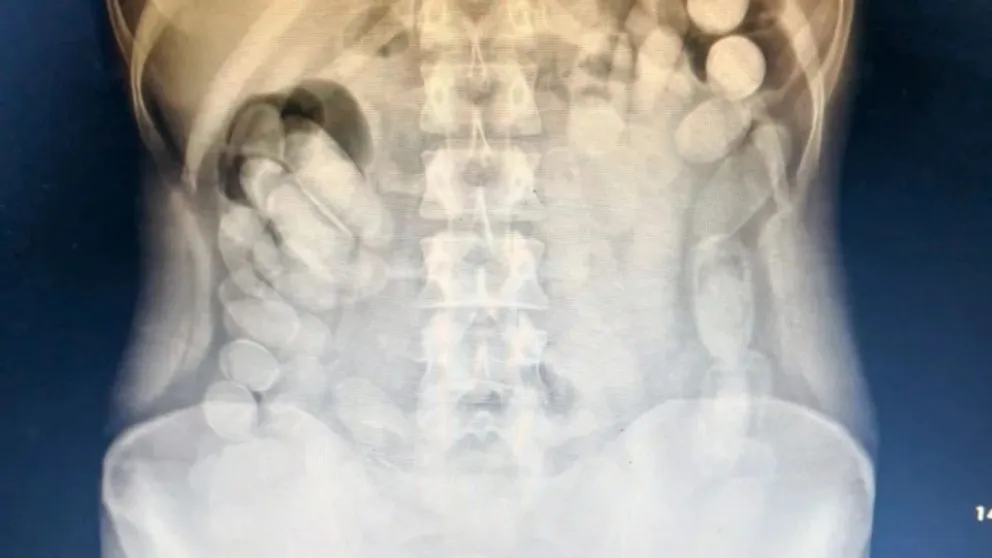

Una vez en el centro médico, al realizarle una radiografía, se confirmó la presencia de varias cápsulas en el tracto abdominal de la mujer. Bajo la supervisión médica adecuada, la ciudadana pudo evacuar un total de 106 cápsulas adicionales, complementando las 12 anteriormente encontradas en su bolso de mano.

En conjunto, las autoridades expropiaron un total de 118 envoltorios cilíndricos que, tras una prueba de campo Narcotest, dieron positivo para cocaína. En total, la sustancia incautada alcanzó un peso de 1 kilo 388 gramos. Esta detención no sólo destaca las estrategias valientes de la fuerza de seguridad sino también expone los métodos alarmantes empleados por los narcotraficantes para introducir estupefacientes en el país. El destino de la mujer ahora está en manos del sistema judicial que ordenó su arresto y la confiscación de toda la sustancia incautada.